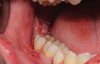

A presurgical rinse of 0.2% chlorhexidine (CHX) solution was performed, followed by administration of local anesthetic using 4% articaine with epinephrine solution. A crestal incision with a vertical releasing incision at the mesial aspect of the surgical area was made, and a full-thickness mucoperiosteal flap was elevated (Figure 1). A buccal and, if required, distal osteotomy was performed using a round carbide bur on a straight handpiece. When necessary the tooth was dissected to allow it to be elevated and extracted (Figure 2). When performing the third molar extraction care was taken to not damage the adjacent second molar tooth nor its supporting alveolar bone. The extraction socket was thoroughly debrided with hand instruments and rinsed with a 0.2% CHX solution to decrease bacteria in the socket (Figure 3).35

Fig 1. Impacted mandibular third molar showing mesial angular orientation after flap elevation to expose the tooth in preparation for extraction.

Figure 1